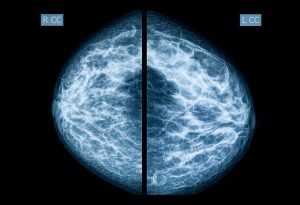

El cáncer de mama es un gran negocio, y la mamografía es una de sus principales fuentes de utilidades. Esta es la razón por la cual la industria está luchando con uñas y dientes para mantenerla al minimizar o simplemente ignorar sus riesgos significativos.

En los Estados Unidos, se recomienda que a partir de los 40 años las mujeres se realicen una mamografía anual, ignorando por completo las recomendaciones establecidas por la Comisión de Servicios Preventivos de los Estados Unidos.

Por desgracia, muchas mujeres desconocen por completo que la ciencia simplemente no respalda el uso de las mamografías de rutina como un medio para prevenir la muerte por cáncer de mama.

Como se reveló en un metaanálisis del año 2011 que fue realizado por la Base de Datos de Revisiones Sistémicas Cochrane, la mamografía de detección de cáncer provocó un 30 % de sobrediagnóstico y tratamiento excesivo, lo cual equivale a un aumento del 0.5 % en el riesgo absoluto.

Para lograr una imagen tridimensional, la máquina se mueve en un arco alrededor del pecho y toma múltiples rayos X durante el proceso que luego se computarizan en conjunto como una imagen en 3D. Esta tecnología recibió la aprobación de la FDA en el 2011, y ahora se encuentra disponible en 46 estados de nuestro país, ¿pero debería estarlo?

Considero que la implementación de los mamogramas 3D es bastante inquietante si toma en cuenta el hecho de que el riesgo principal de las imágenes bidimensionales convencionales es la radiación ionizante.

Debido a que la mamografía 3D requiere vistas múltiples para lograr la tridimensionalidad, es lógico que la dosis total de radiación de la mamografía 3D sea considerablemente más alta que la de una mamografía 2D estándar.

Sabemos que todos los niveles de radiación ionizante pueden causar cáncer, pero, sorprendentemente, los radiólogos aún quieren que las personas con mamas densas o un área de sospecha primero se realicen una mamografía tradicional, luego de una mamografía 3D con tomosíntesis.